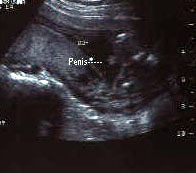

الولد

الأسبوع ال17